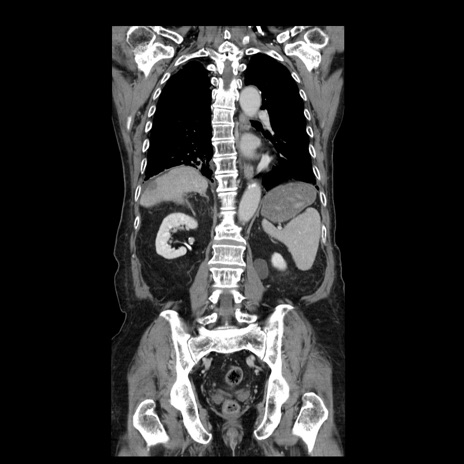

症例21(冠状断像)

【症例】70歳代男性

【主訴】腹痛

【現病歴】肝硬変・肝細胞癌にてかかりつけの方。約9時間前に食後より腹痛出現。症状が徐々に増悪し、嘔吐出現したため来院。

【既往歴】肝硬変、肝細胞癌(RFA、TACE後)

【身体所見】意識清明、表情苦悶様、BT 36℃、BP 129/78mmHg、P 88bpm、SpO2 97%(RA)、右上腹部から心窩部にかけて圧痛あり、反跳痛なし、筋性防御あり。

【データ】WBC 5800、CRP 0.16